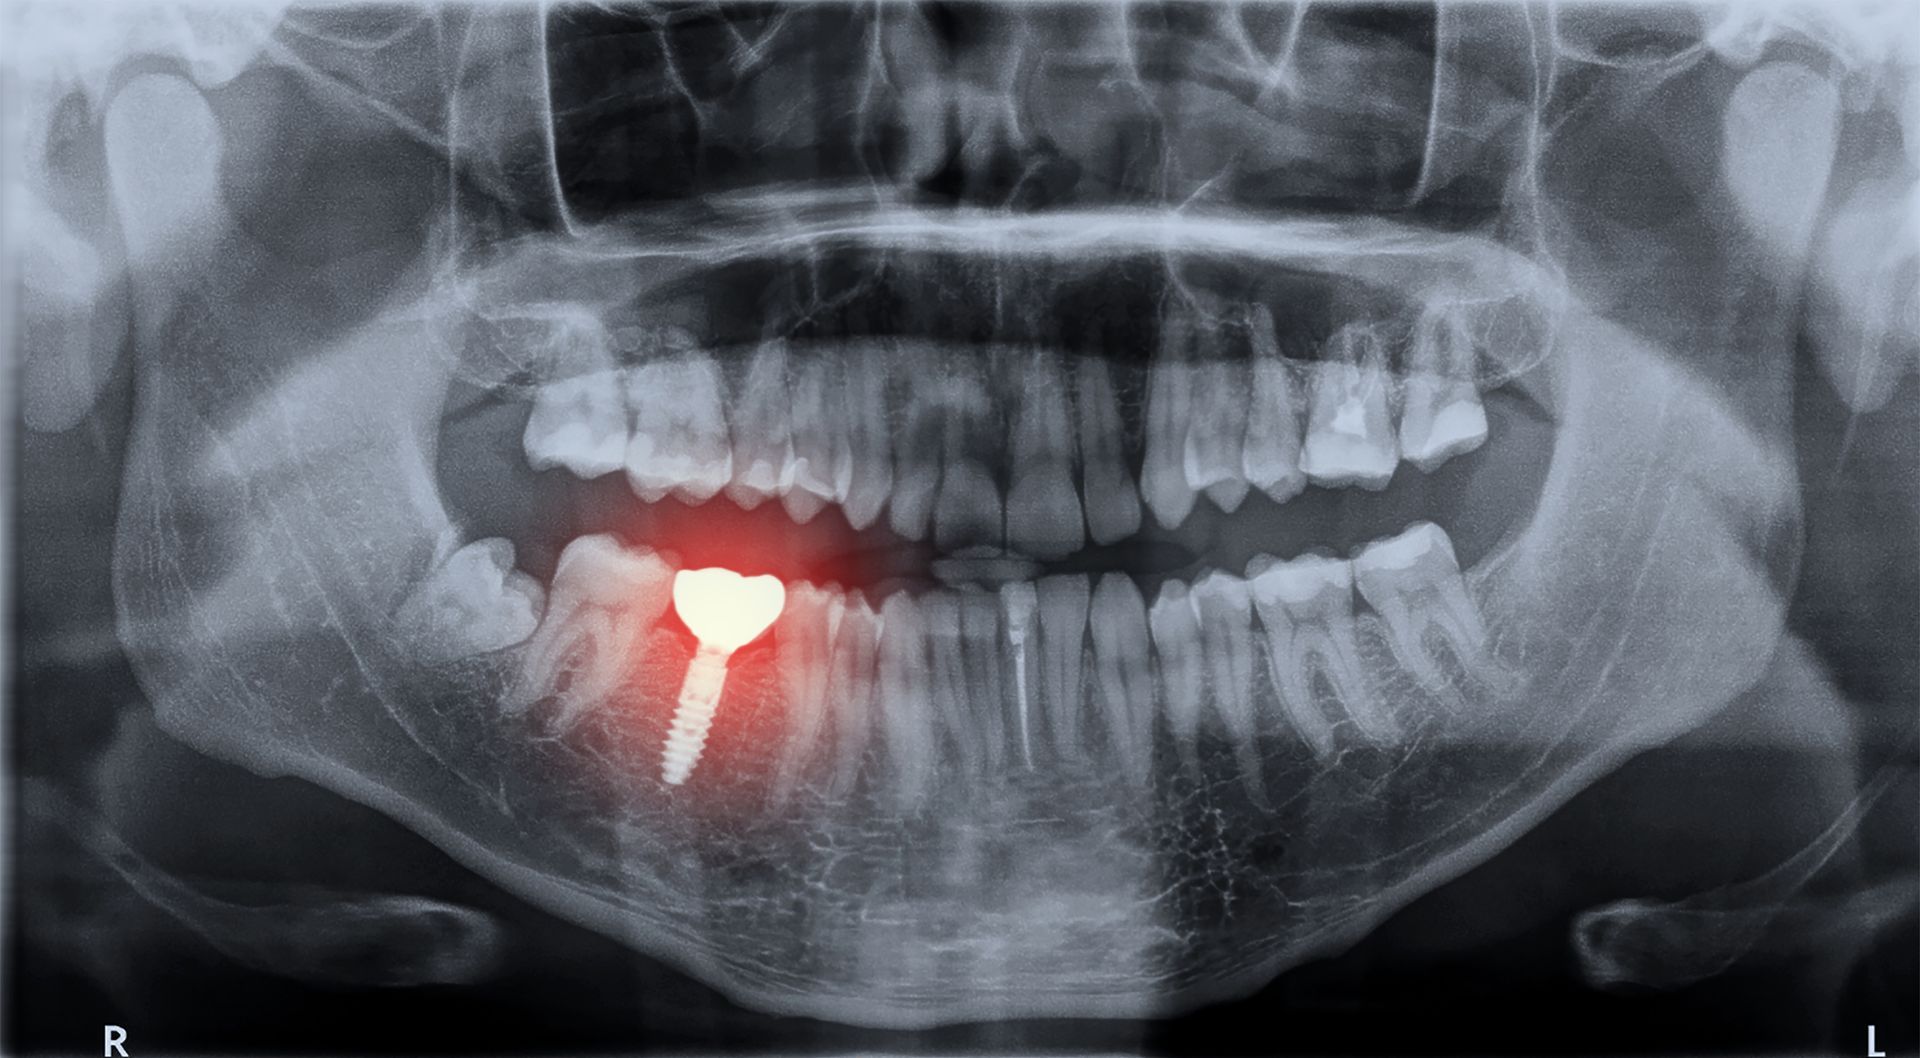

Implantologie

Nous offrons le service de restaurations sur

implant, la couronne ou le pont sur implant étant la solution de choix pour remplacer une dent manquante.